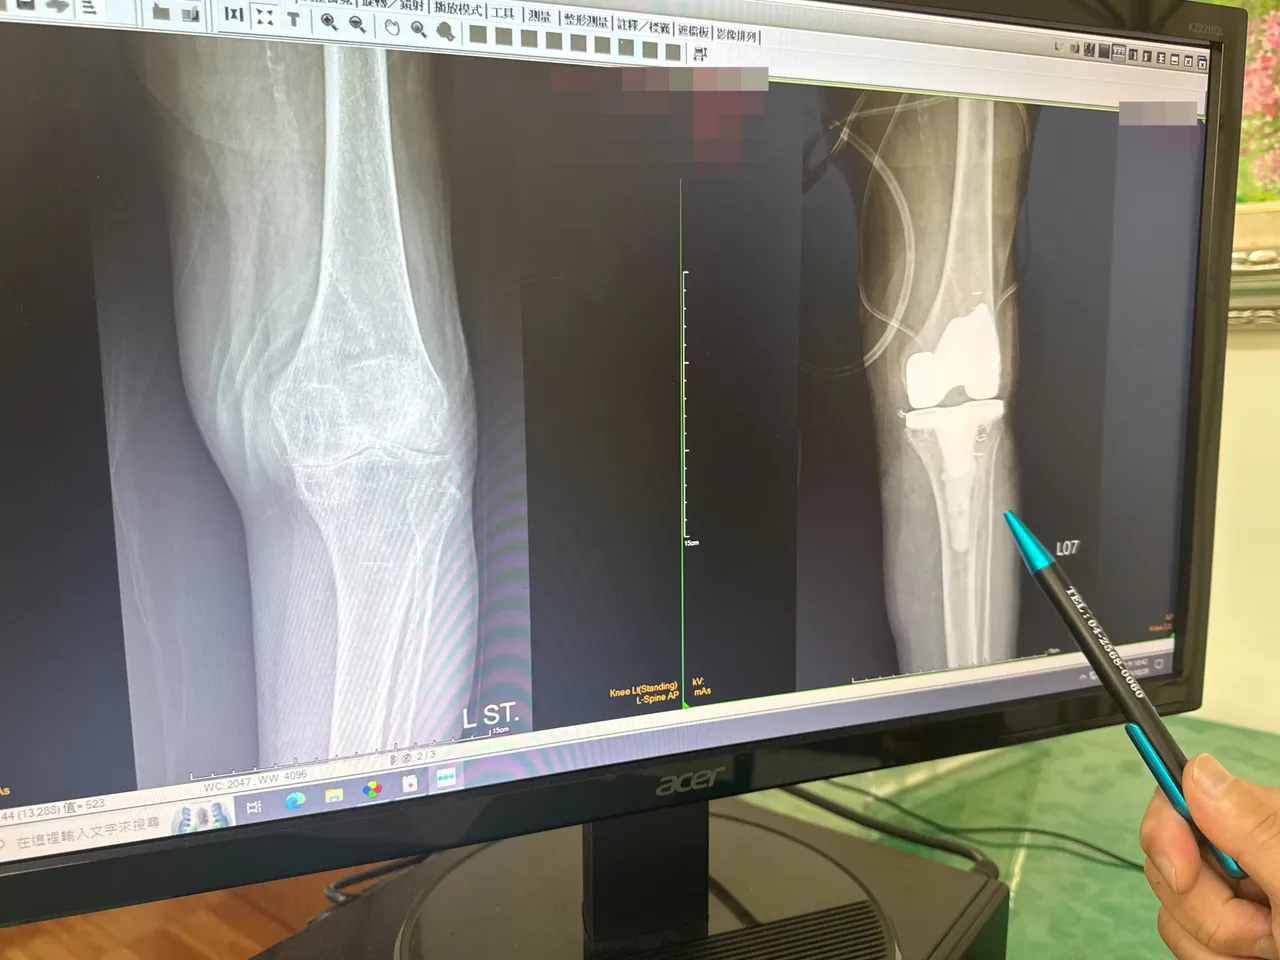

百歲人瑞左膝關節退化,置換人工關節(右)。院方提供